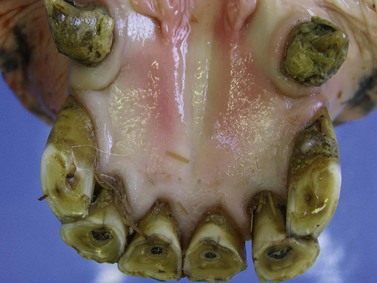

A post-mortem survey of dental disease in geriatric donkeys (estimated median age 31 years) showed a very high prevalence (93 %) of dental disease; with diastemata (85 %), missing (56 %), displaced (43 %) and worn teeth (34 %) being the most common dental disorders present30 (Fig. 18.11). Studies in horses have also shown an increased prevalence of dental disease in older age groups.1,2,3133 A comparison of clinical dental disorders in different age groups of donkeys (age range 2–53) showed a significant increase in the prevalence of dental disease in donkeys over 20 years of age (≥88 % prevalence) compared to donkeys younger than 20 years (≤64 %).4 More specifically, a significant increase in the prevalence of diastemata, missing teeth, overgrown teeth, worn teeth, displaced teeth, and periodontal disease with increasing age has been shown, in particular in donkeys over 20 years of age.4 As expected, the prevalence of enamel points decreased significantly with age, to a prevalence of less than 20 % in donkeys older than 20 years, as compared to >40 % prevalence in donkeys under 20 years of age.4

image

Fig. 18.11 Severe bilateral lateral displacement of the 310 and 410 is present in this 38-year-old donkey. There is also moderate lateral displacement of the 407.